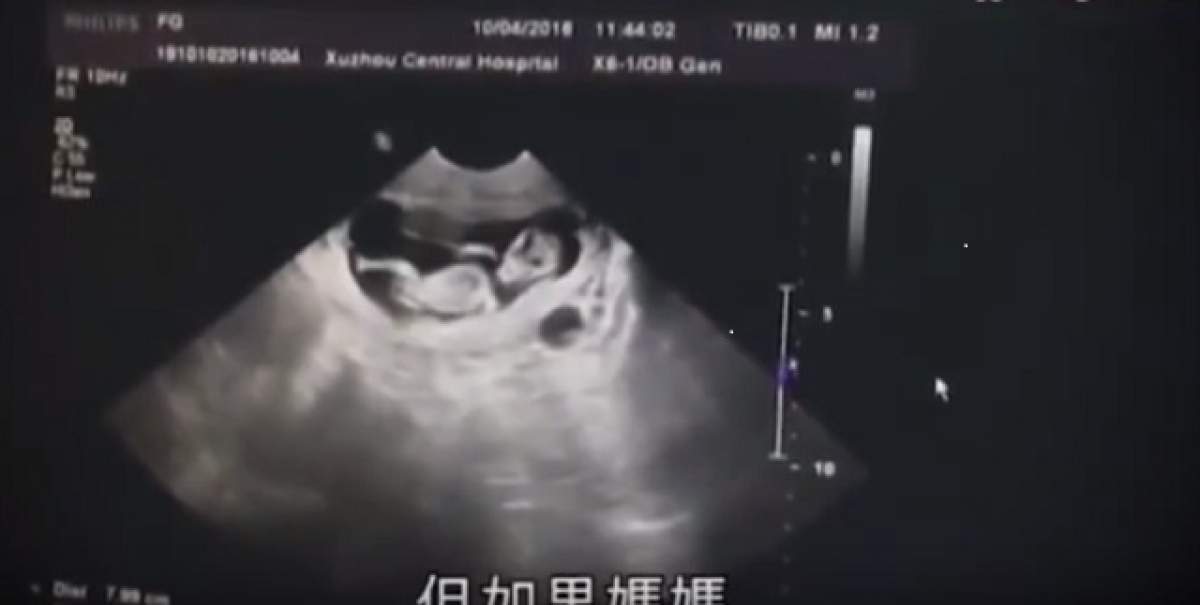

Situaţie bizară într-un spital din oraşul chinezesc Xuzhou. Un bărbat în vârstă de 40 de ani şi-a adus la spital fiica de 12 ani, care era însărcinată. Bărbatul a încercat să îi păcălească pe medicii spunându-le că aceasta ar fi de fapt soţia sa, în vârstă de 20 de ani.

Fetiţa de 12 ani a fost adusă la spital de către părinţi, iniţial aceştia spunând că sunt soţul şi soacra acesteia. Micuţa era gravidă în luna a treia, iar burta era deja destul de vizibilă, porivit The Sun.